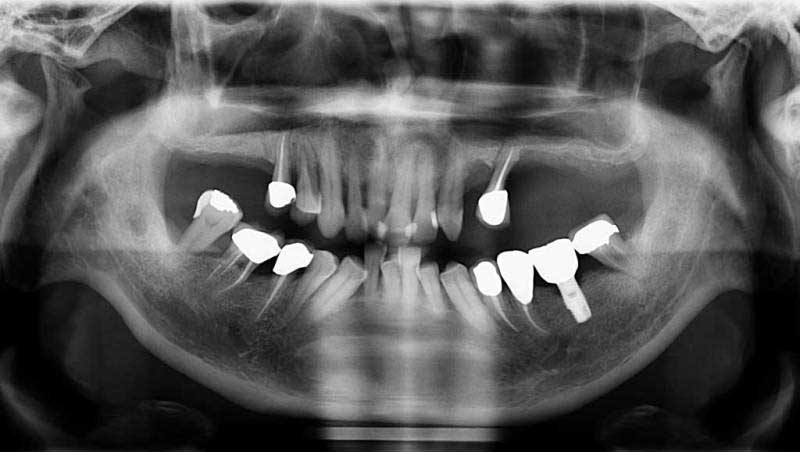

鼻竇增高術術後